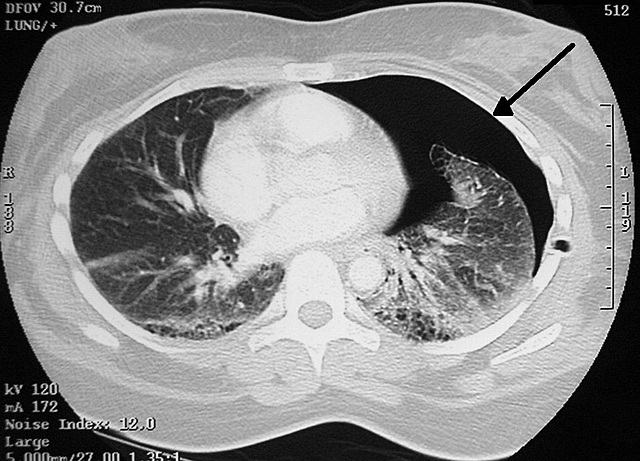

• TC en tórax

TC en tórax

Se utiliza en: 1) Hemorragia intratorácica.

2) Detectar enfermedades del corazón: neurismas de la aorta, calsificación de la arteria coronaria.

3) Émbolos pulmonares.